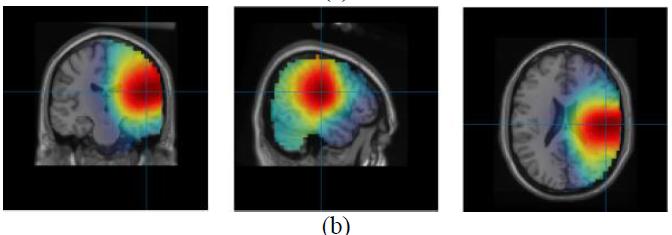

CREDIT: Yunlong ShaoCould artificial intelligence help solve the mental health crisis? What if an algorithm allowed neurologists to know the area affected by a brain seizure?

These are just two of the questions that Maryam Ravan, Ph.D., assistant professor of electrical and computer engineering, aims to address. Working on two separate studies, she proposes the use of cutting-edge algorithms and techniques that could provide noninvasive solutions for clinicians to treat neurological and psychiatric conditions more effectively.

Normal brain activity, including mood and thinking processes, relies on a balance of fast and slow brain waves. Imbalanced brain wave activity is associated with neurological issues such as epilepsy and psychiatric conditions like bipolar disorder and major depressive disorder.

One technique clinicians use to detect brain wave imbalances is electroencephalography (EEG). This diagnostic test uses sensors to measure the electrical activity on a patient’s scalp, which is representative of the brain wave activity taking place underneath. Brain wave data collected through an EEG holds valuable information regarding an individual’s neurological and mental health. Existing software models that process EEG brain wave data use a mathematical technique called exact low-resolution brain electromagnetic tomography (eLORETA).

In collaboration with McMaster University psychiatrist Gary M. Hasey, M.D., Ravan co-authored two studies that leverage machine learning, a form of artificial intelligence (AI), to improve the treatment of mental health conditions.

In one study, Ravan helped develop a machine learning algorithm to analyze patients’ brain waves and categorize their patterns as biomarkers for bipolar disorder or major depressive disorder.

The researchers pose that, given its abilities, machine learning could be useful in analyzing a patient’s EEG results and determining whether a patient is experiencing bipolar disorder or major depressive disorder. With Ravan’s expertise, the team developed a new algorithm called ReLORETA, which accounts for multiple variables known to impact brain source estimates, including head geometry and misaligned brain electrodes, among other factors.

“The accuracy of our algorithm, which was derived from a large sample of patients, successfully distinguished bipolar disorder from major depressive disorder more accurately than

the existing methods available to clinicians,” says Ravan. “This suggests that our method may hold significant promise as a clinical tool.”

A second mental health study explores how brain wave data could be used to predict how patients with major depressive disorder will respond to the antidepressant sertraline (sold under the brand name Zoloft) versus a placebo treatment.

While antidepressants are often the first line of treatment for major depressive disorder, it can take months of trial and error and multiple medications before reaching an effective treatment. If predictive biomarkers can inform how a patient will likely respond to a certain treatment, clinicians may be able to eliminate this frustrating process and fast-track a patient’s recovery time.

The study’s other co-authors include College of Engineering and Computing Sciences alumni Thomas Oakley (M.S. ’22), Jonathan Coskuner (M.S. ’21), and Andrew Cadwallader (M.S. ’22).